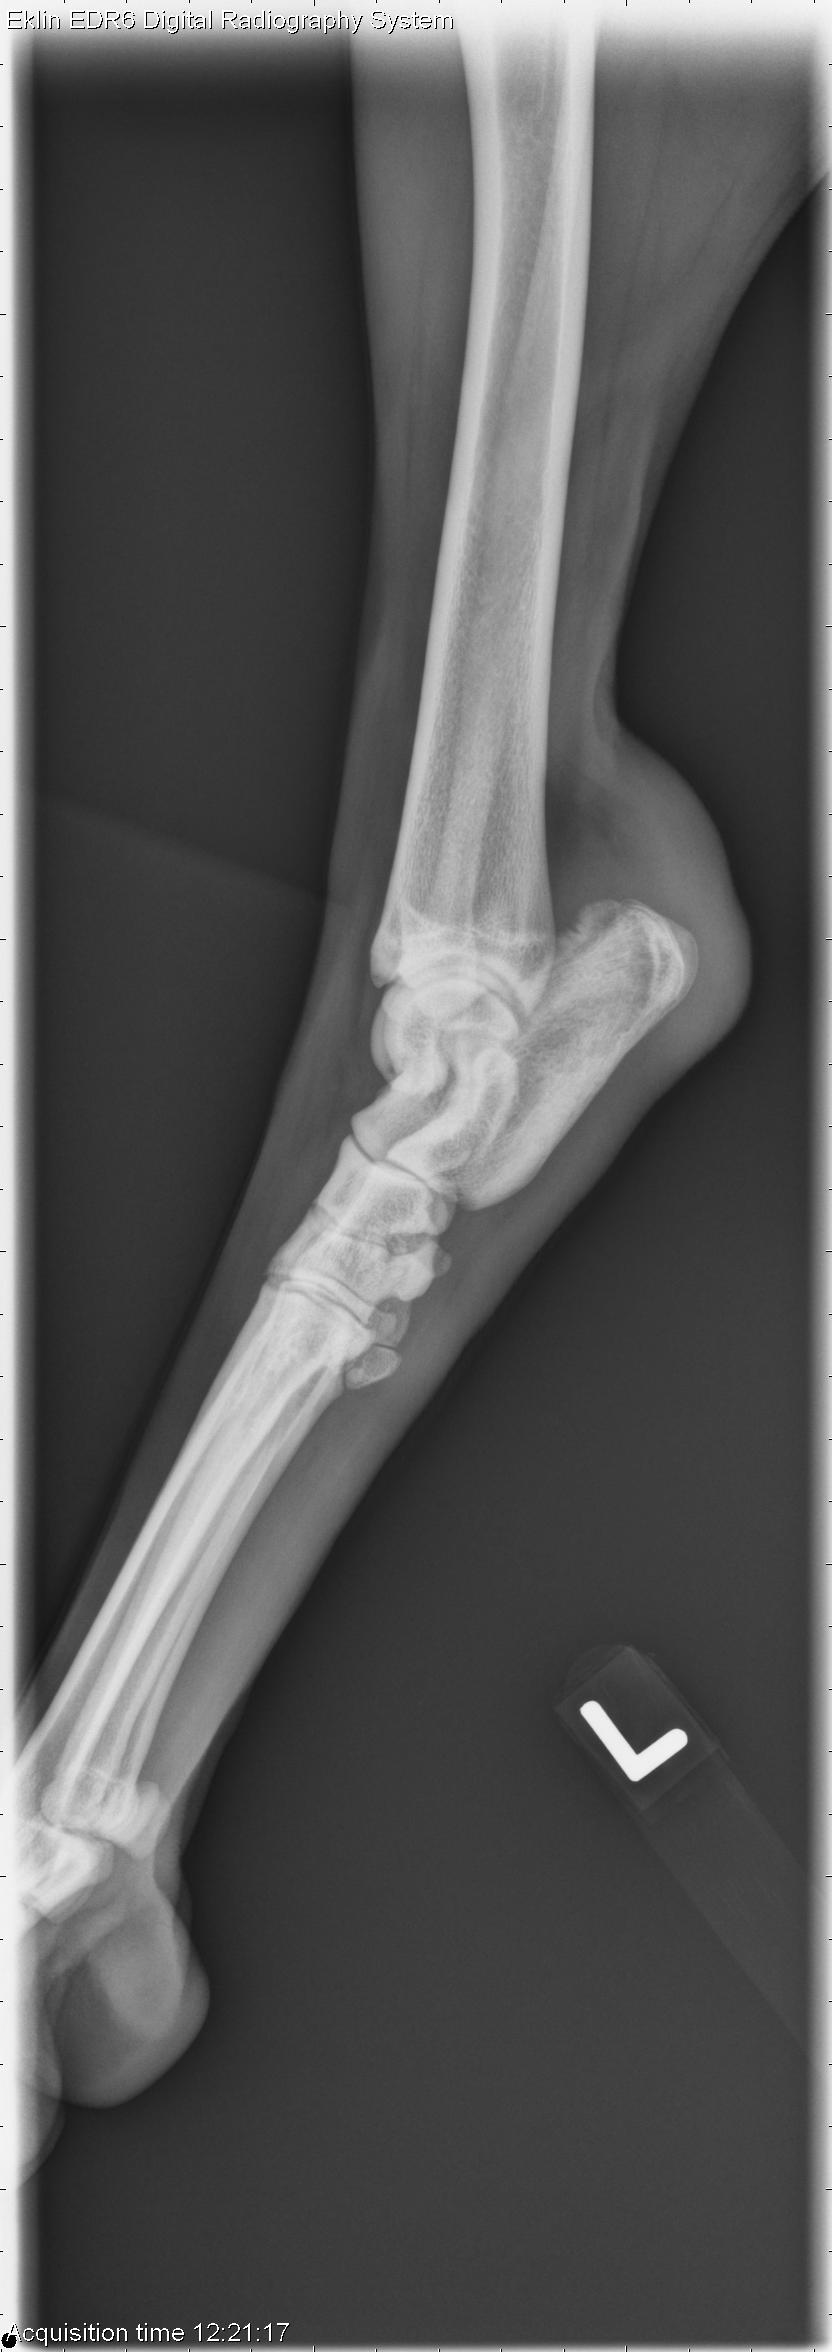

This week’s case is a 3-year-old male Rhodesian Ridgeback with swelling of the left tarsus and recent anorexia. What are your interpretations?

L LAT Hind

Tarsus – There is an aggressive bone lesion of the lateral and mid to proximal aspect of the left calcaneus. There is cortical destruction and marked, irregular periosteal proliferation. There is associated extracapsular soft tissue swelling at this site. There is a small, elongated mineral fragment within this soft tissue. the calcaneal tendon is thickened and irregular.